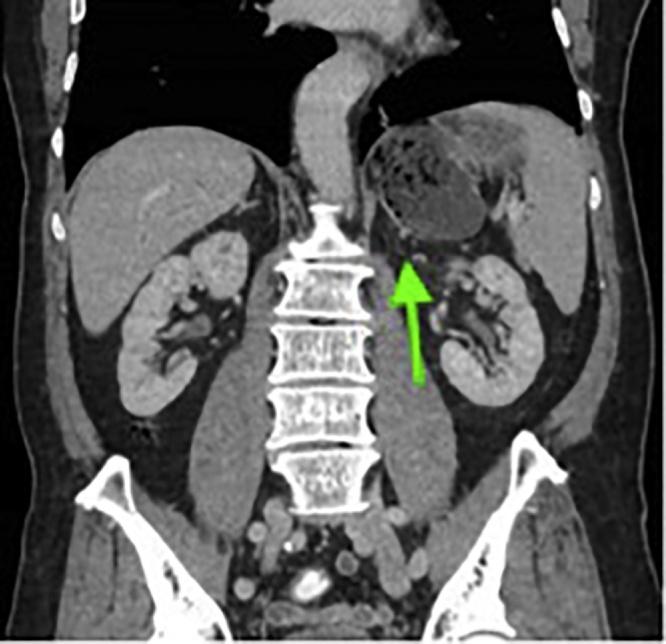

CASE PRESENTATION

A 77-year-old gentleman presented to the outpatient clinic with a one-month history of passing black stools. He was arranged for an oesophagogastroduodenoscopy (OGD) which revealed a gastric body polyp and a diverticulum in the fundus of the stomach.

一名77岁男性到门诊就诊,有一个月排黑便病史。他接受了食管胃十二指肠镜检查(OGD),结果显示胃体部有息肉,胃底部有一个憩室。